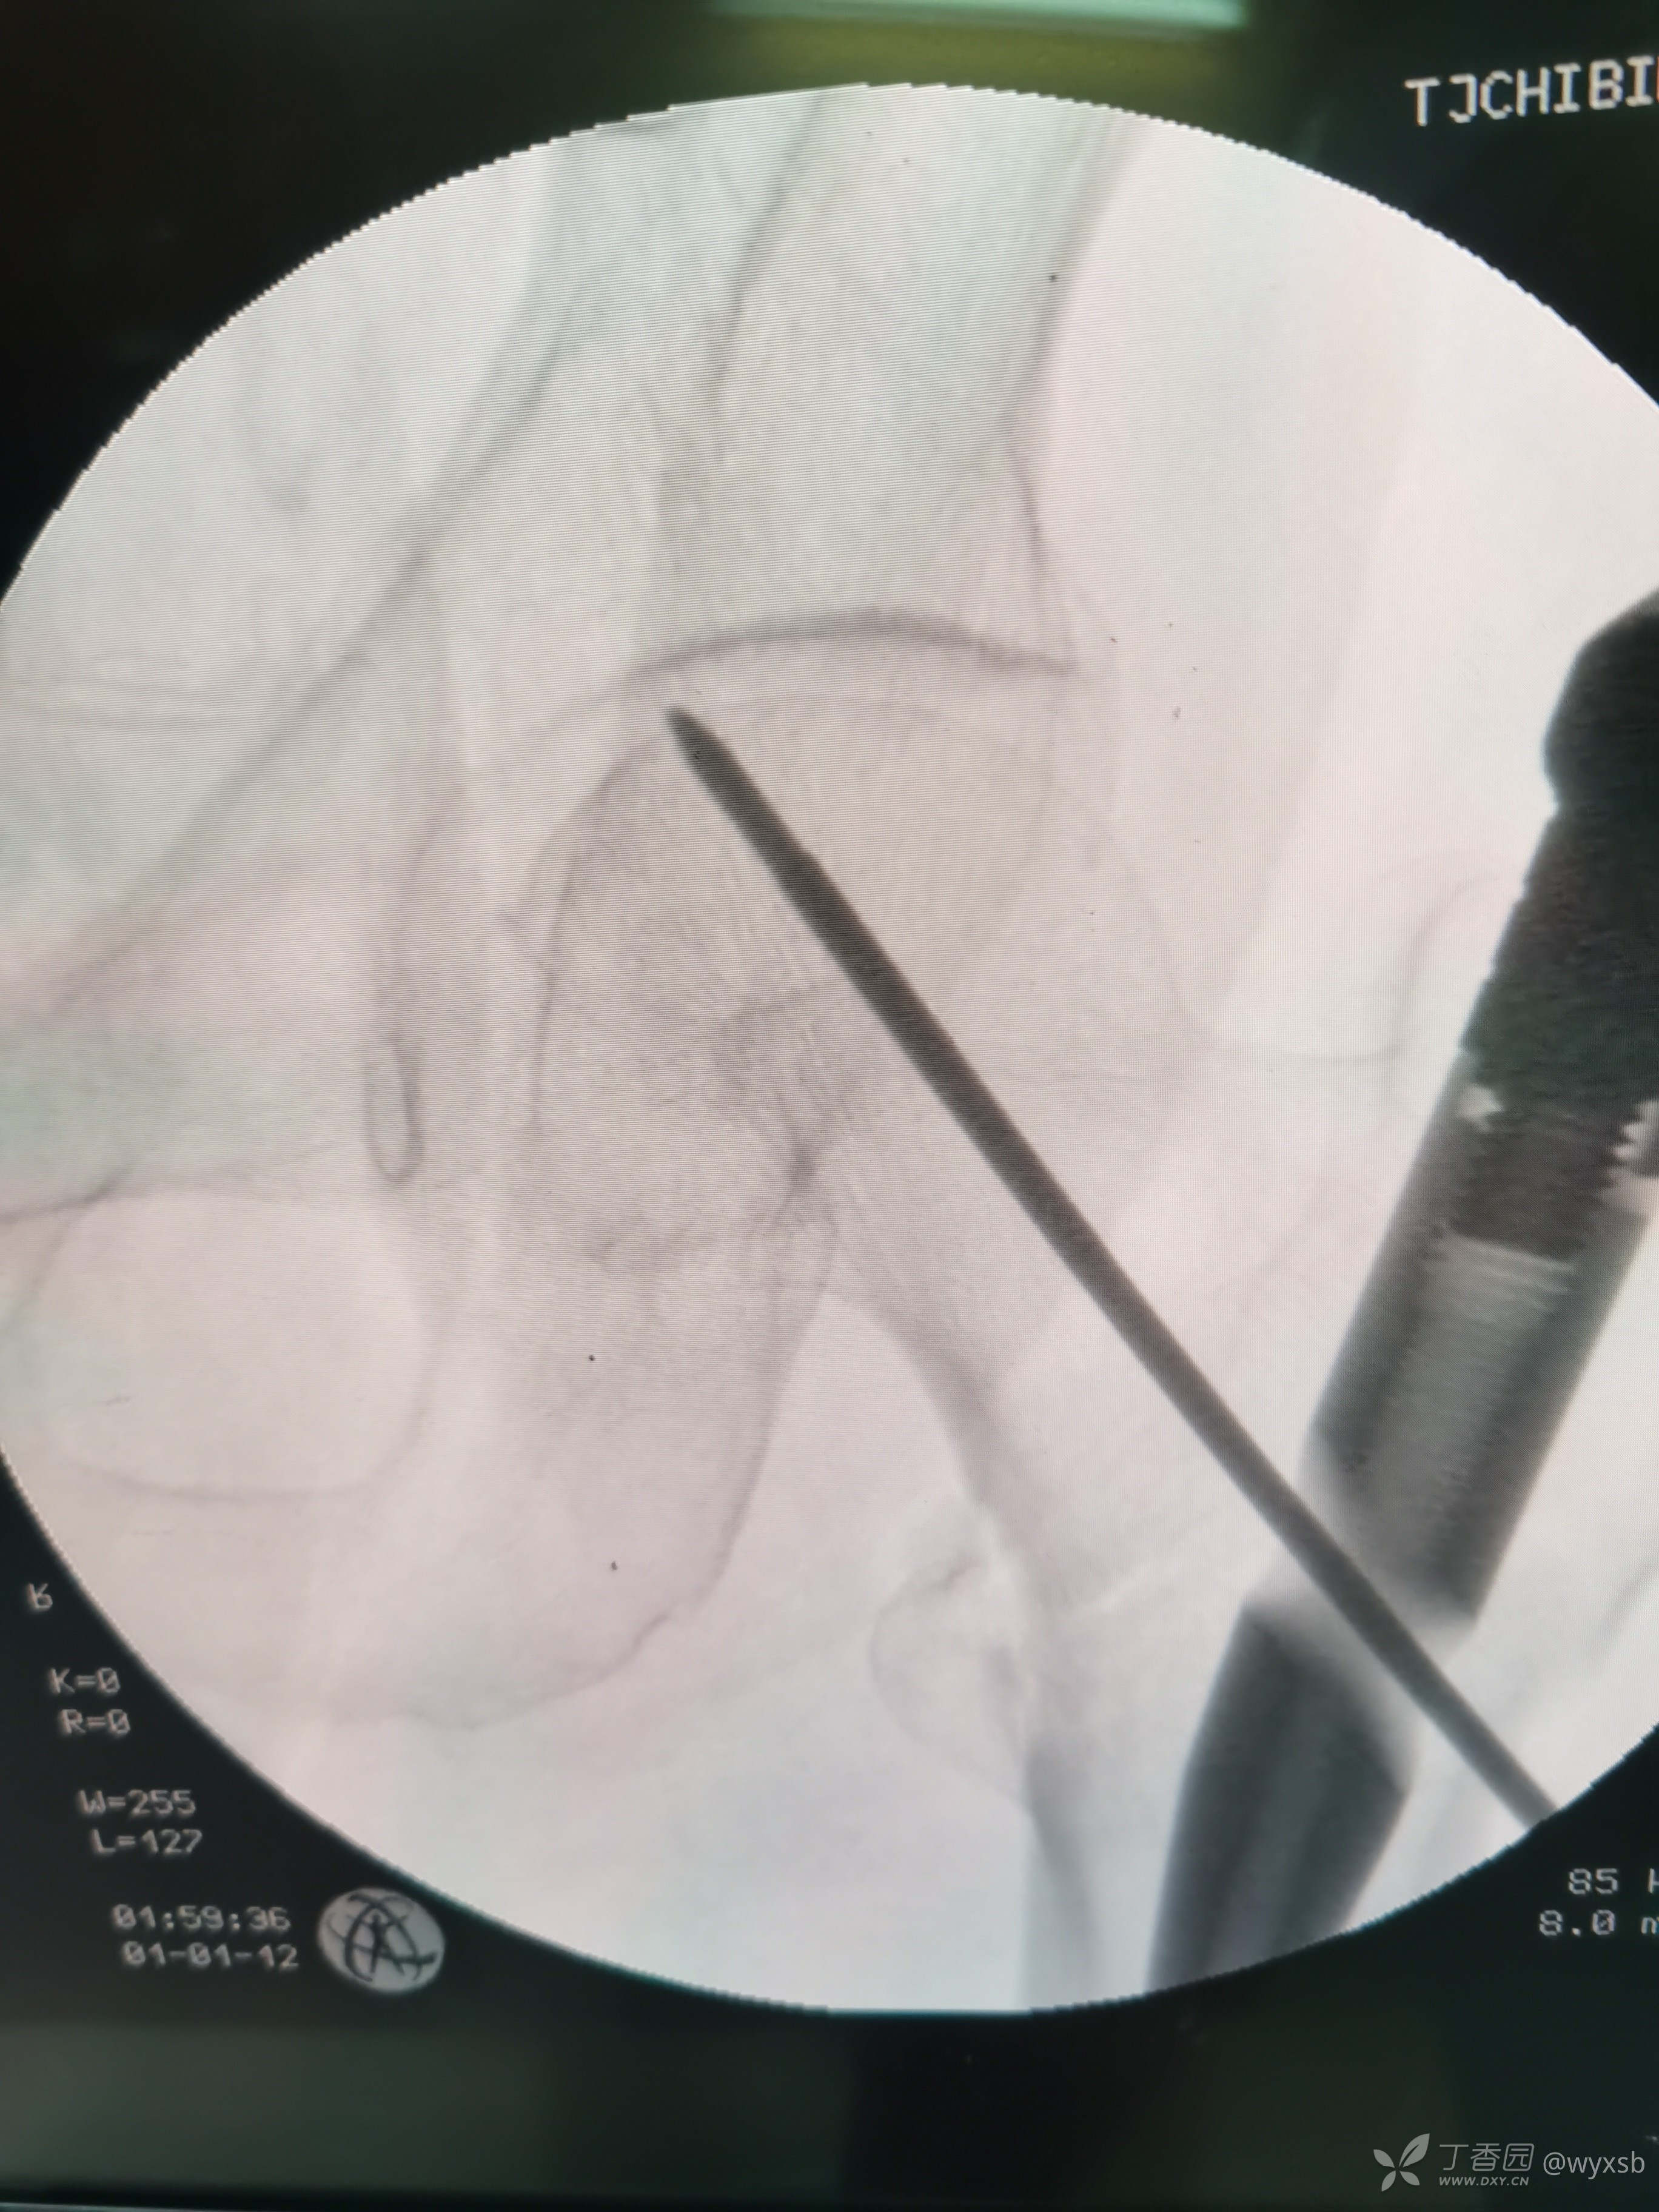

术中植钉情况

术中透视